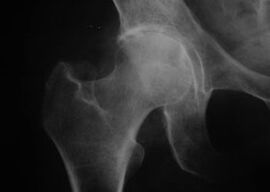

Coxathrosis, Arthrosis na hadin gwiwar hip

X-ray na haɗin gwiwa tare da Arthrosis

Tare da wannan cuta, ana lura da hoton asibiti na al'ada na Arthrosis.

Alamar farko ta coxarthrosis shine rashin jin daɗi a cikin haɗin gwiwa bayan aiki na jiki.

Tare da cigaban coxarthrosis, zafi yana ƙaruwa, taurin kai da iyakance motsi sun bayyana.

Marasa lafiya tare da matsanancin nau'i na coxarthrosis ya kiyaye reshe da abin ya shafa, ka guji yaduwa a kai, kuma yayin da yake tsawanta, zabi mukamai a ciki.